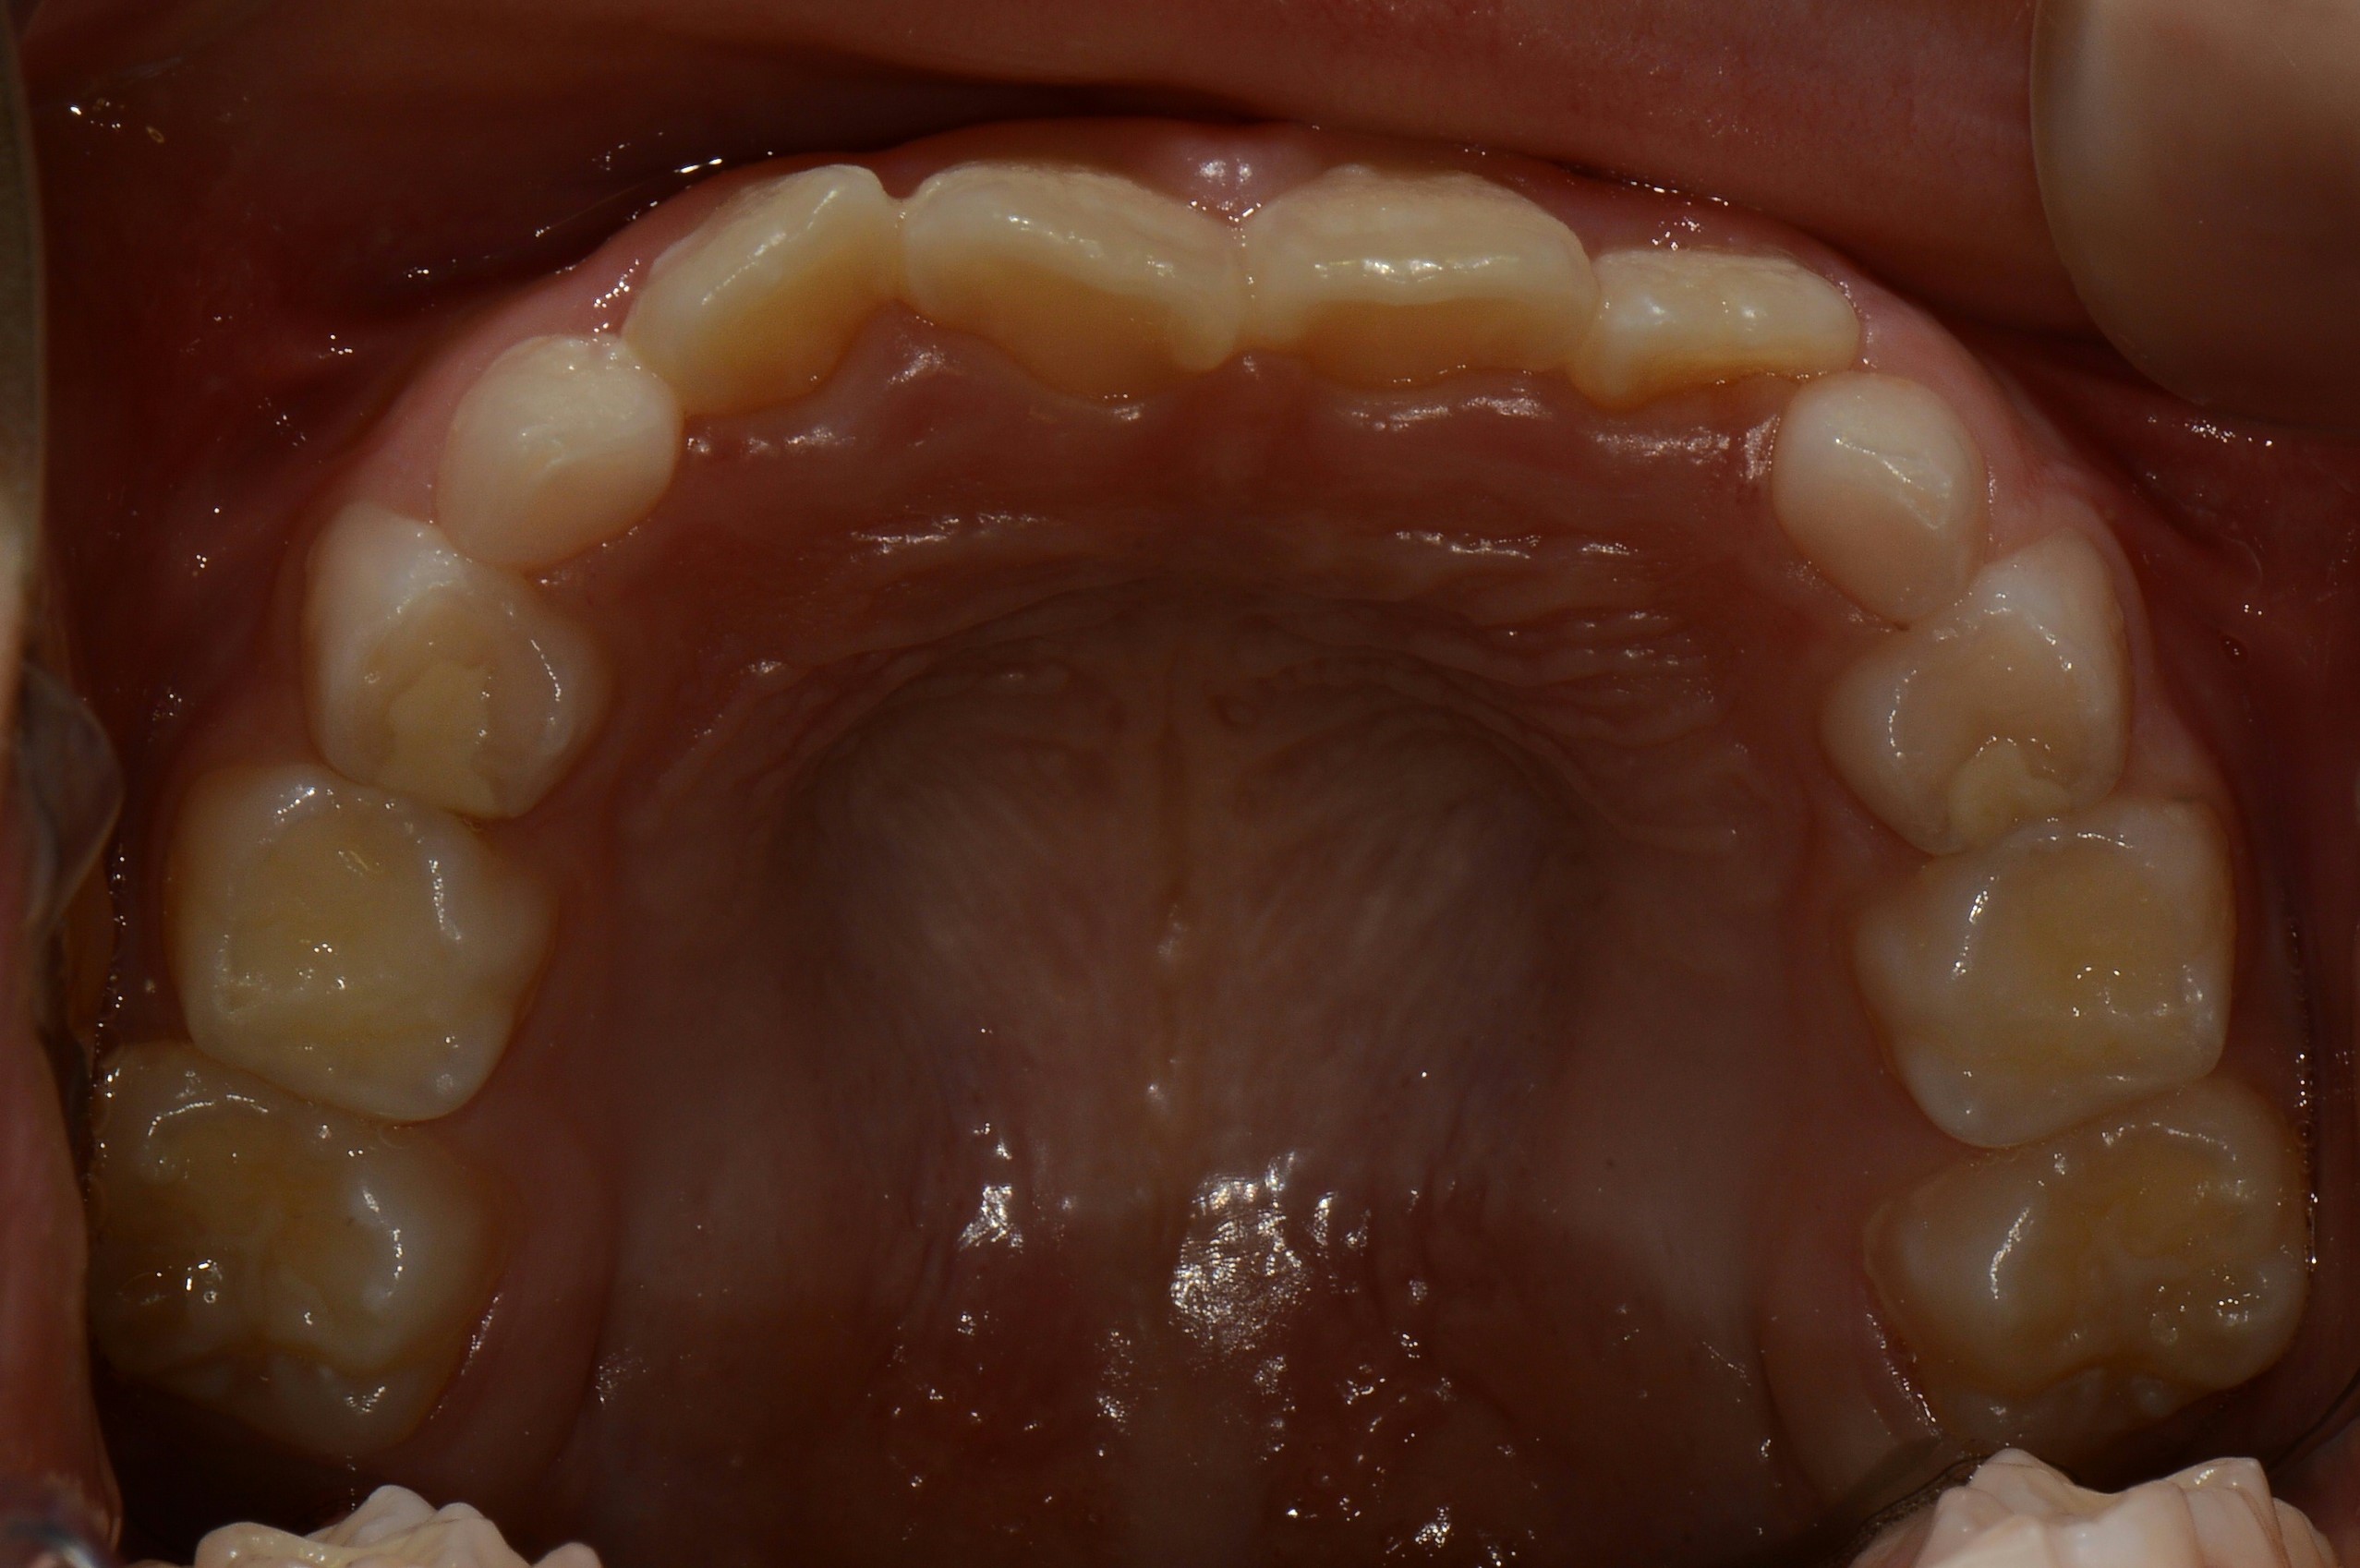

치료 전 사진입니다.